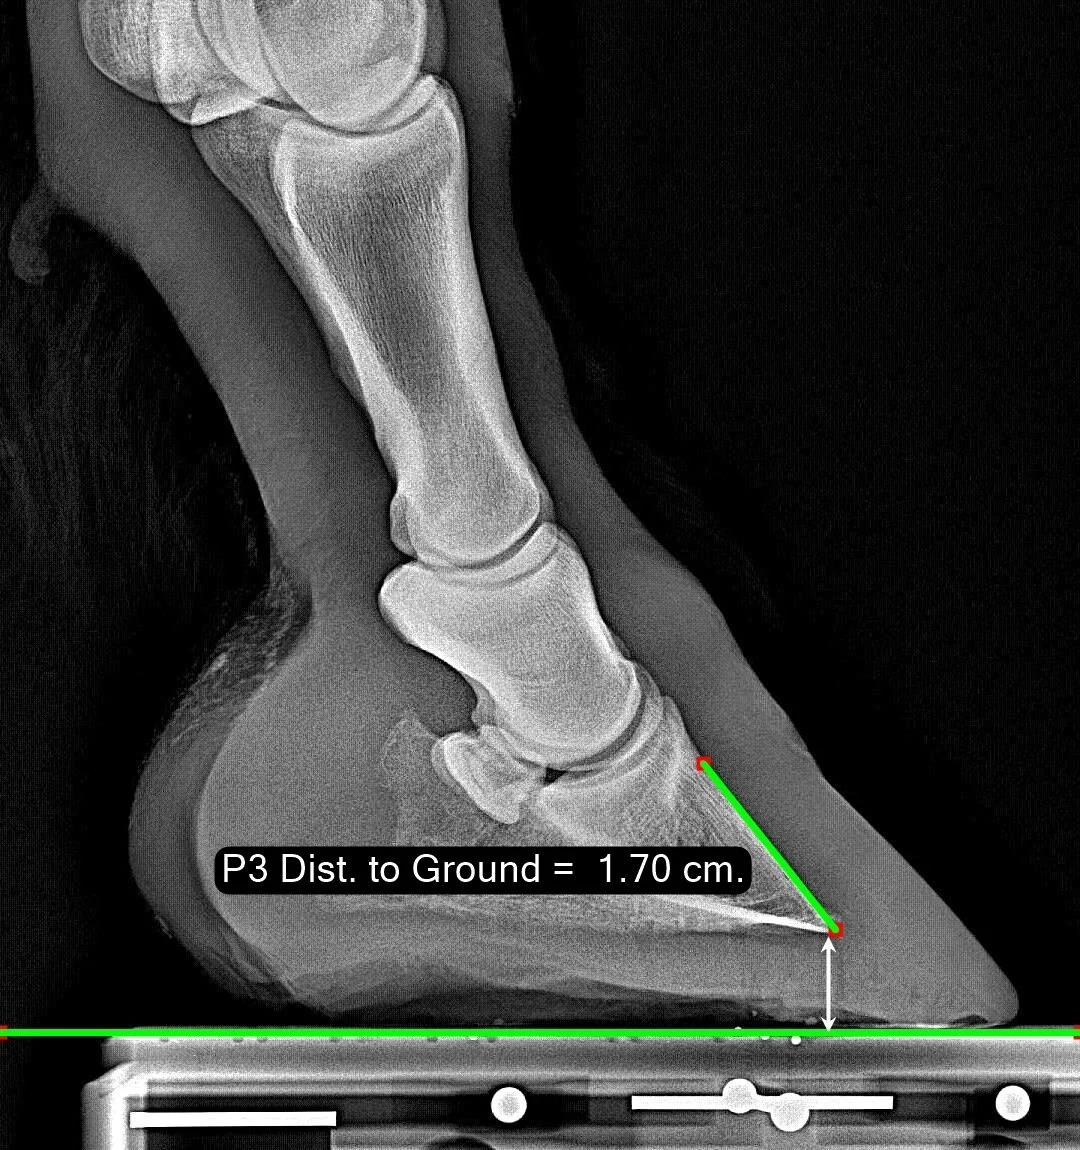

P3 Distance to Ground

This measure is related to sole thickness beneath the tip of P3. Due to varying quality of radiographs, we have not felt that we should expect to be able to see the underside of the actual sole, so rather than trying, we measure “distance to ground” to give an estimate of sole thickness conflated with concavity of the sole. We do not want this measure to be too small.

Normal Range

If you look carefully at this distribution, you will see that it appears to be two ‘bell curves’ superimposed. This is because a portion of our database was barefoot, and a portion had a shoe - which raised the ‘P3 Distance to Ground’ by the shoe thickness. Again, this linear measure has been scaled by the length of P2. This histogram is not shown in our reports due to the possible confusion it might cause with shod-vs-barefoot.